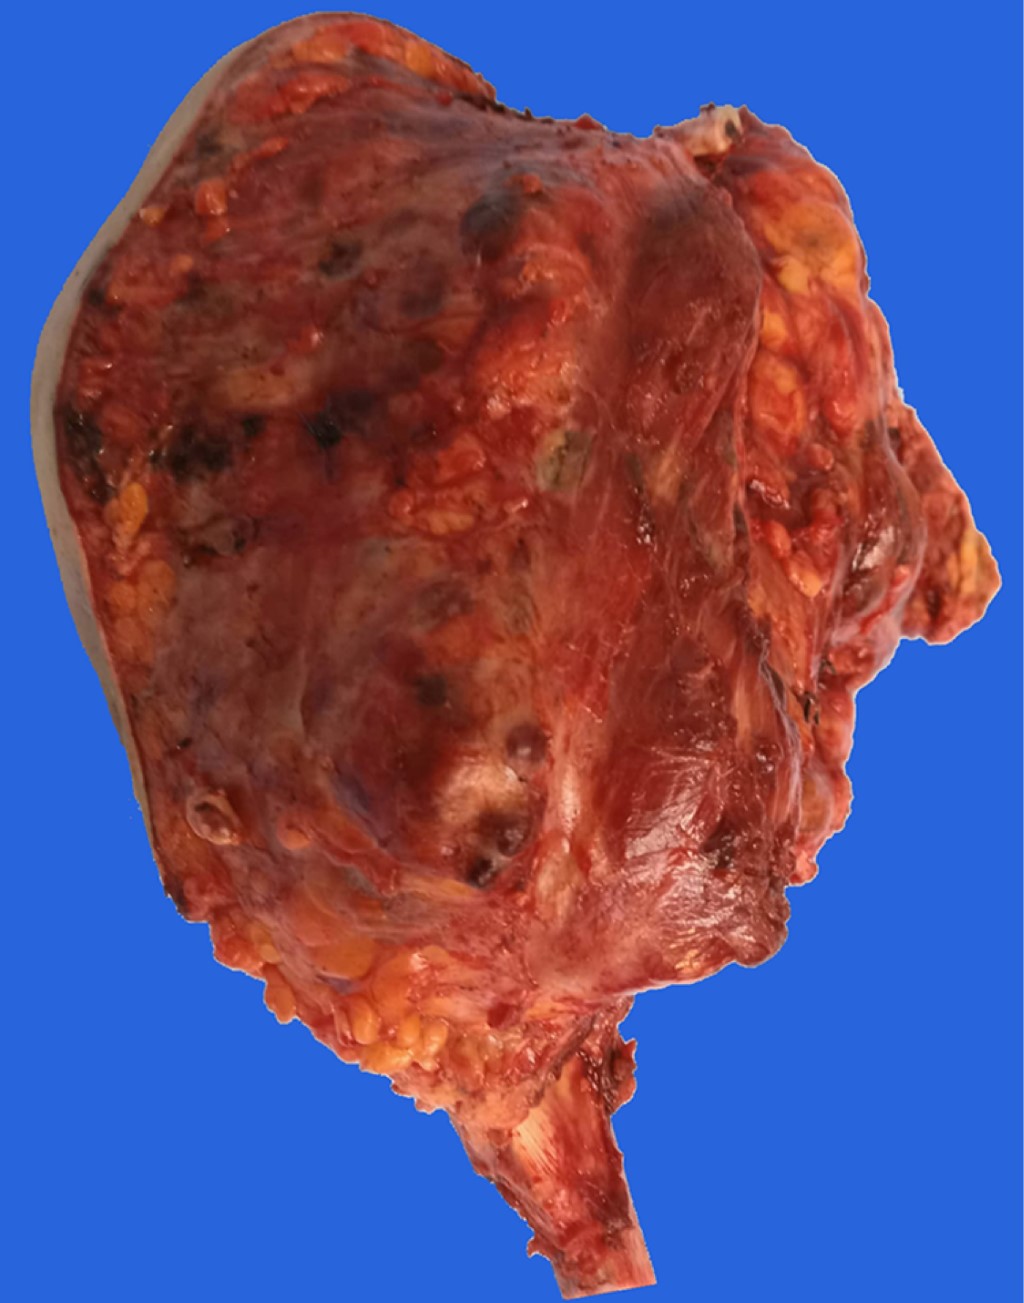

Paciente femenino de 17 años de edad, diestra, estudiante, que es enviada al Servicio de Ortopedia Pediátrica a consecuencia de tumor en el húmero proximal derecho. A simple vista se presenta importante aumento de volumen en el hombro derecho, así como limitación funcional principalmente a la abducción del hombro, así como parestesias distales. La función de hombro, muñeca y mano está conservada. Es difícil establecer el tiempo de evolución de la enfermedad, ya que existen contradicciones entre la versión de la paciente y la de sus padres; sin embargo, se considera que es de aproximadamente nueve meses, siendo su primera manifestación el aumento de volumen con progresiva disminución a la abducción. Esta lesión no había recibido tratamiento previo. Radiológicamente se trata de lesión osteolítica expansiva que muestra pérdida de la cortical y una sombra correspondiente a invasión neoplásica hacia los tejidos blandos circundantes (Figura 1). Tanto por tomografía como por resonancia magnética se observa el componente extracompartimental de la lesión, invasión articular y también a la escápula a expensas de permeación a la cortical anterior de la misma, así como gran desplazamiento medial de las estructuras neurovasculares, replegándolas hacia la parrilla costal (Figura 2). Una vez realizados estudio y análisis clínico e imagenológico, se realiza biopsia, la cual reporta tumor óseo de células gigantes. Se discute el caso y se llega a la conclusión de que la mejor alternativa terapéutica es una resección extraarticular de escápula con inclusión de más de la mitad proximal del húmero derechos. Previo al procedimiento quirúrgico se les informa detalladamente a los padres y a la paciente sobre el mismo, quienes lo autorizan. Dicho procedimiento se cataloga como resección tipo VI B de Malawer. El acto quirúrgico se llevó a cabo sin complicaciones, comentando que el grupo muscular de flexores del codo precisó de su resección en su mitad proximal, por lo que el remanente distal se reinsertó sobre la delgada fascia anterior del brazo (Figuras 3 y 4). Se inmovilizó la extremidad superior de la paciente por tres semanas y posteriormente se inició programa para reinicio de la función de la extremidad dentro de los rangos que la resección realizada permitió. A tres meses del evento quirúrgico, la función obtenida se estableció como 25/30 basados en el MSTS score (Figura 5). A los seis meses de vigilancia postoperatoria, por medio de tomografía computada, se detectó una lesión compatible con metástasis única pulmonar basal en el hemitórax derecho. Se revisaron estudios preoperatorios, no encontrándose indicio de que se tratara de una lesión ya existente al diagnóstico. Se solicitó valoración por cirugía oncológica, quienes determinan la realización de una minitoracotomía para realizar la metastatectomía correspondiente; se confirmó sospecha diagnóstica.

Figura 3

Figura 4